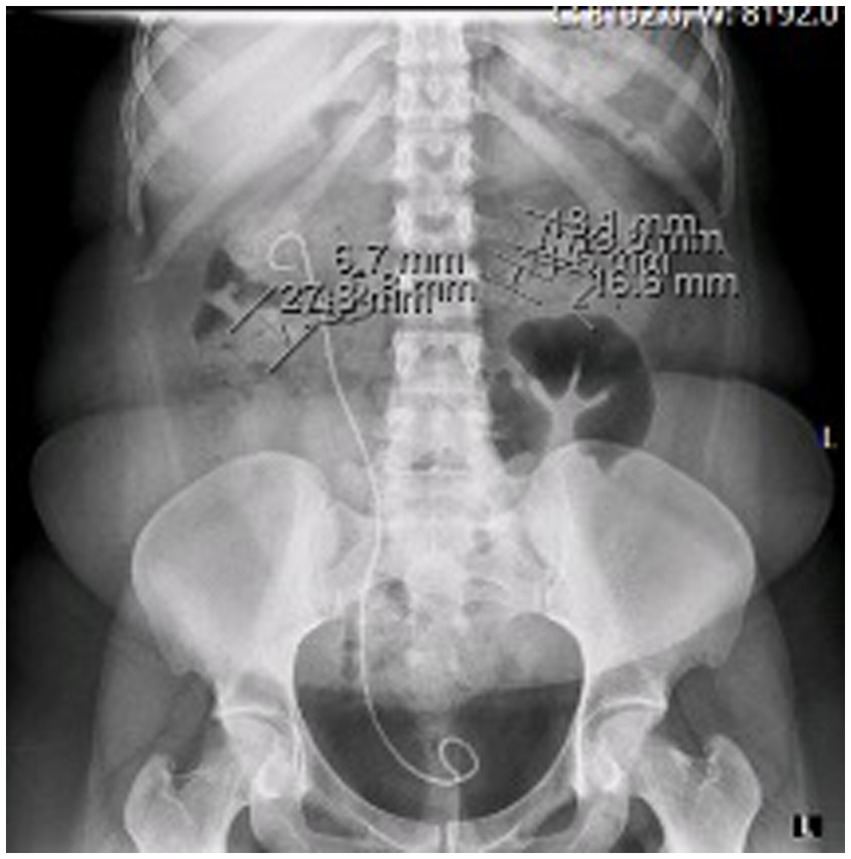

At the time of presentation in our hospital, her kidney function was mildly reduced (eGFR 86 mL/min/1.73m2) without albuminuria or proteinuria. Ultrasound showed a normal left kidney without signs of lithiasis, while the right kidney had a slightly reduced parenchyma of 10 mm and 3rd degree hydronephrosis. CT scan confirmed hydronephrosis of the right kidney with an impacted stone in the pyelon. Dynamic scintigraphy showed significant functional damage (25%) of the right kidney. After spontaneous expulsion, the stone was sent for analysis that revealed cysteine formations. The case was discussed with the urological team, and in May 2021, a right percutaneous nephrostomy was performed due to obstruction with atrophy of the parenchyma. Dynamic scintigraphy after the procedure showed no improvement in the right kidney function. She was hospitalized in August 2021 for right pyelotomy with ureteral stenting (double J stent) and removal of nephrostomy. One month later she presented with a UTI and worsening kidney function with eGFR of 23 mL/min/1.73m2. CT scan showed multiple stones of the left kidney in the lower and middle calyces and cast stones in the lower columns and pyelon. The right kidney was hypotrophic with lobulated contour, signs of post-inflammation changes, and multiple mineral stones along with the previously placed double J stent (Figures 1, 2). Treatment with broad-spectrum antibiotics and hydration was commenced. The right double J stent was replaced and another double J stent was placed in the left kidney. Following treatment, the kidney function started to improve along with a fall in inflammatory markers.

Figure 1

KUB at the time of acute kidney injury.